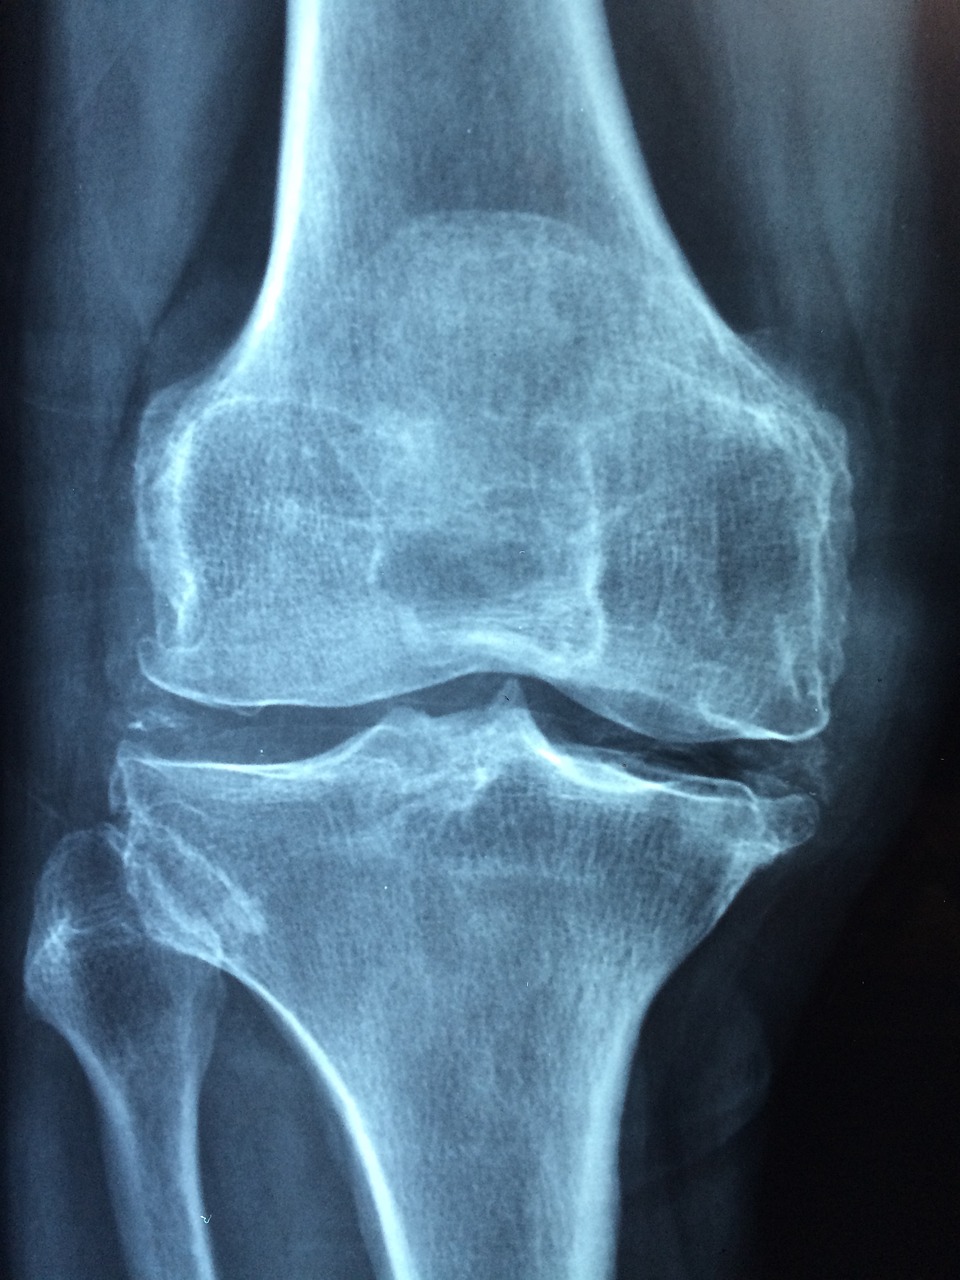

무릎 인공관절 수술은 평균적으로 한쪽 무릎 기준 300만 원 이상의 비용이 들 수 있습니다.

특히 건강보험이 적용되더라도 본인부담금이 꽤 되는 경우가 많아, 경제적 사정이 어려운 분들에겐 진입 장벽이 높을 수밖에 없는데요.

이러한 문제를 해결하기 위해 정부에서는 무릎 인공관절 수술비 일부를 지원하는 복지사업을 운영 중입니다.

- 건강보험 기준 ‘인공관절치환술(슬관절)’ 필요 질환자

※ 병원 진단서 등 '슬관절 인공관절이 필요한 상태'임을 증명할 수 있어야 합니다.

무릎 인공관절 수술은 고통을 줄이고 삶의 질을 크게 향상시키는 치료입니다.